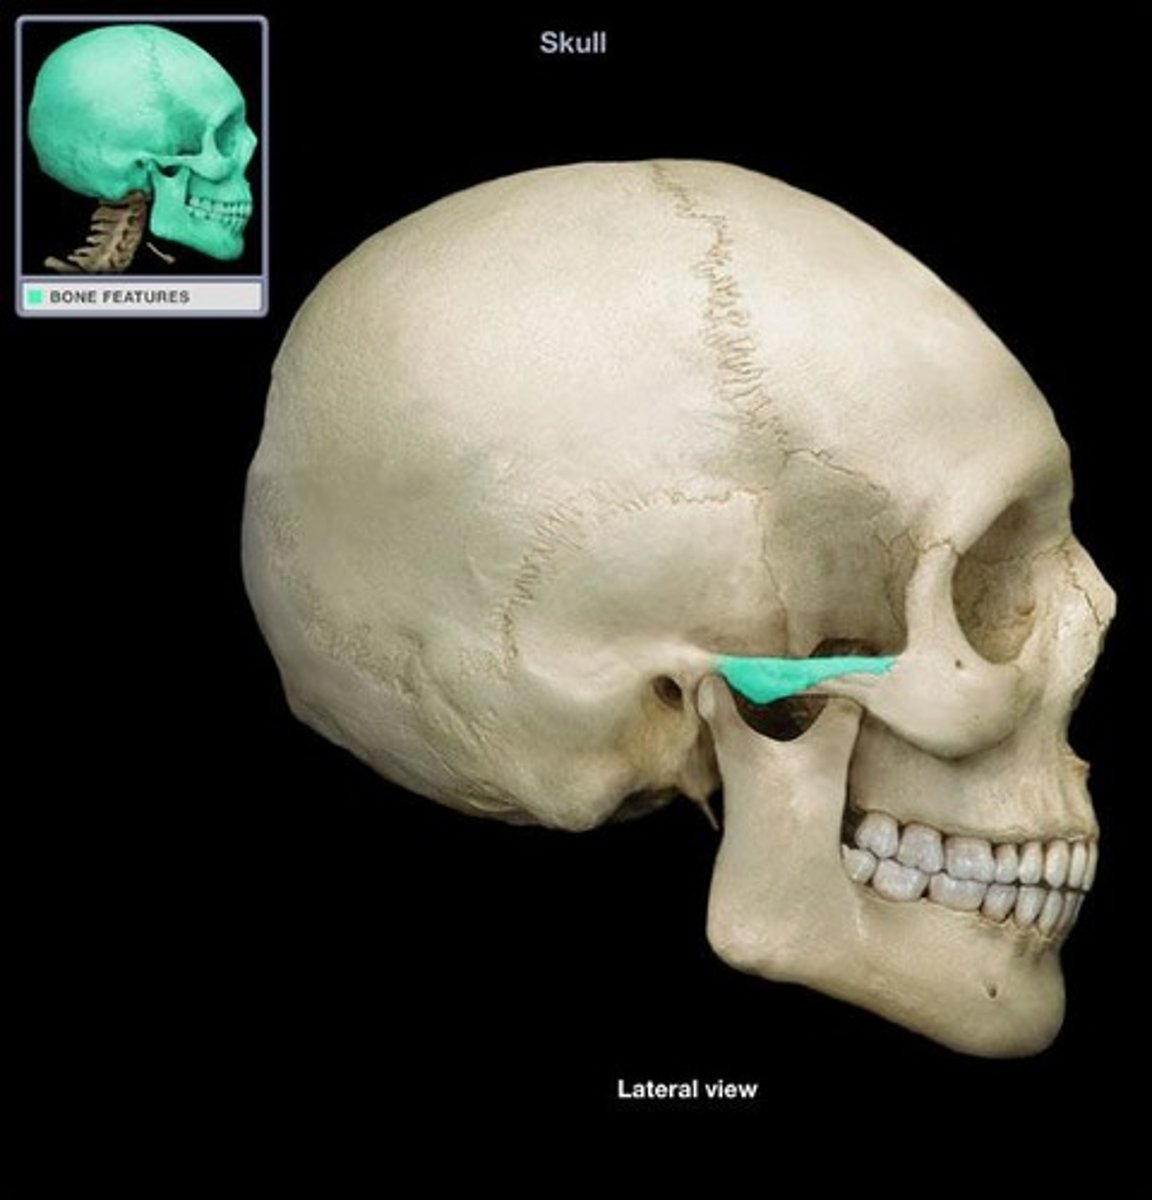

zygomatic bone

temporal process of zygomatic bone

zygomatic arch